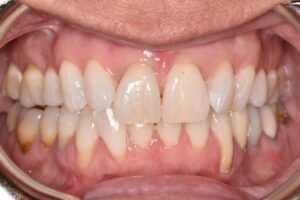

This patient came to us with gum recession, a condition in which the gums pull away from the teeth and expose the roots. Although it may appear to be a cosmetic issue, treating gum recession is medically necessary to prevent root sensitivity, decay, bone loss, and long-term tooth mobility.

Using advanced microsurgical techniques, Dr. Lamas restored healthy gum coverage and rebuilt the protective tissue around the affected teeth. This treatment helps preserve the patient’s oral health, prevent further recession, and maintain long-term comfort and confidence.